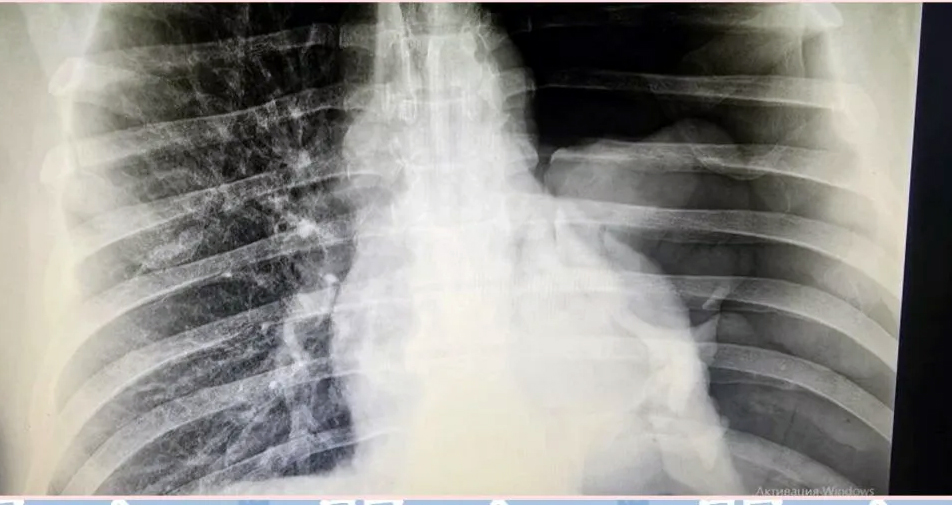

Скрытая угроза: коллапс легкого

49-летний пациент из Маянги упал с двухметровой высоты, но в больницу поехал только через трое суток, когда боль и одышка стали невыносимыми. Диагноз – напряженный тотальный пневмоторакс. Левое легкое полностью коллабировало (сдулось), а плевральная полость заполнилась воздухом, сдавив сердце и сосуды. Хирурги-травматологи экстренно установили дренаж по Бюлау, буквально откачав воздух из грудной клетки. Пациент спасен, но врачи предупреждают: промедление с обращением при такой травме гарантированно ведет к летальному исходу.